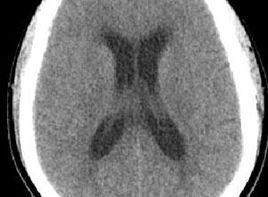

腦室受壓移位:是指CT檢查或腦血管造影發現腦室移位、腦室受壓,多出現在腦外傷或腦腫瘤。